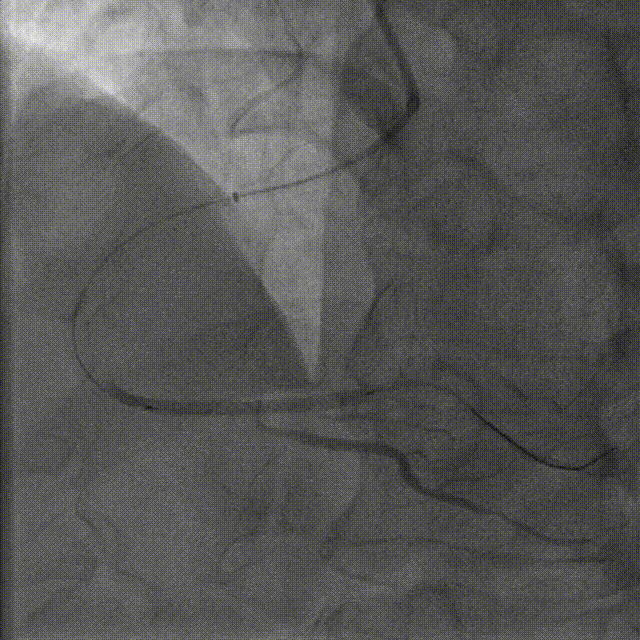

在Telescope™导引延长导管辅助下,于远段至中段病变串联植入支架2.5*38mm、2.5*38mm

在Telescope™导引延长导管辅助下,于右冠脉中段至近段串联植入支架3.0*29mm、3.0*18mm

在Telescope™导引延长导管辅助下,选择2.5*12mm高压球囊、2.75*15mm高压球囊于支架内后扩张

在Telescope™导引延长导管辅助下,选择3.0*15mm高压球囊于支架内后扩张